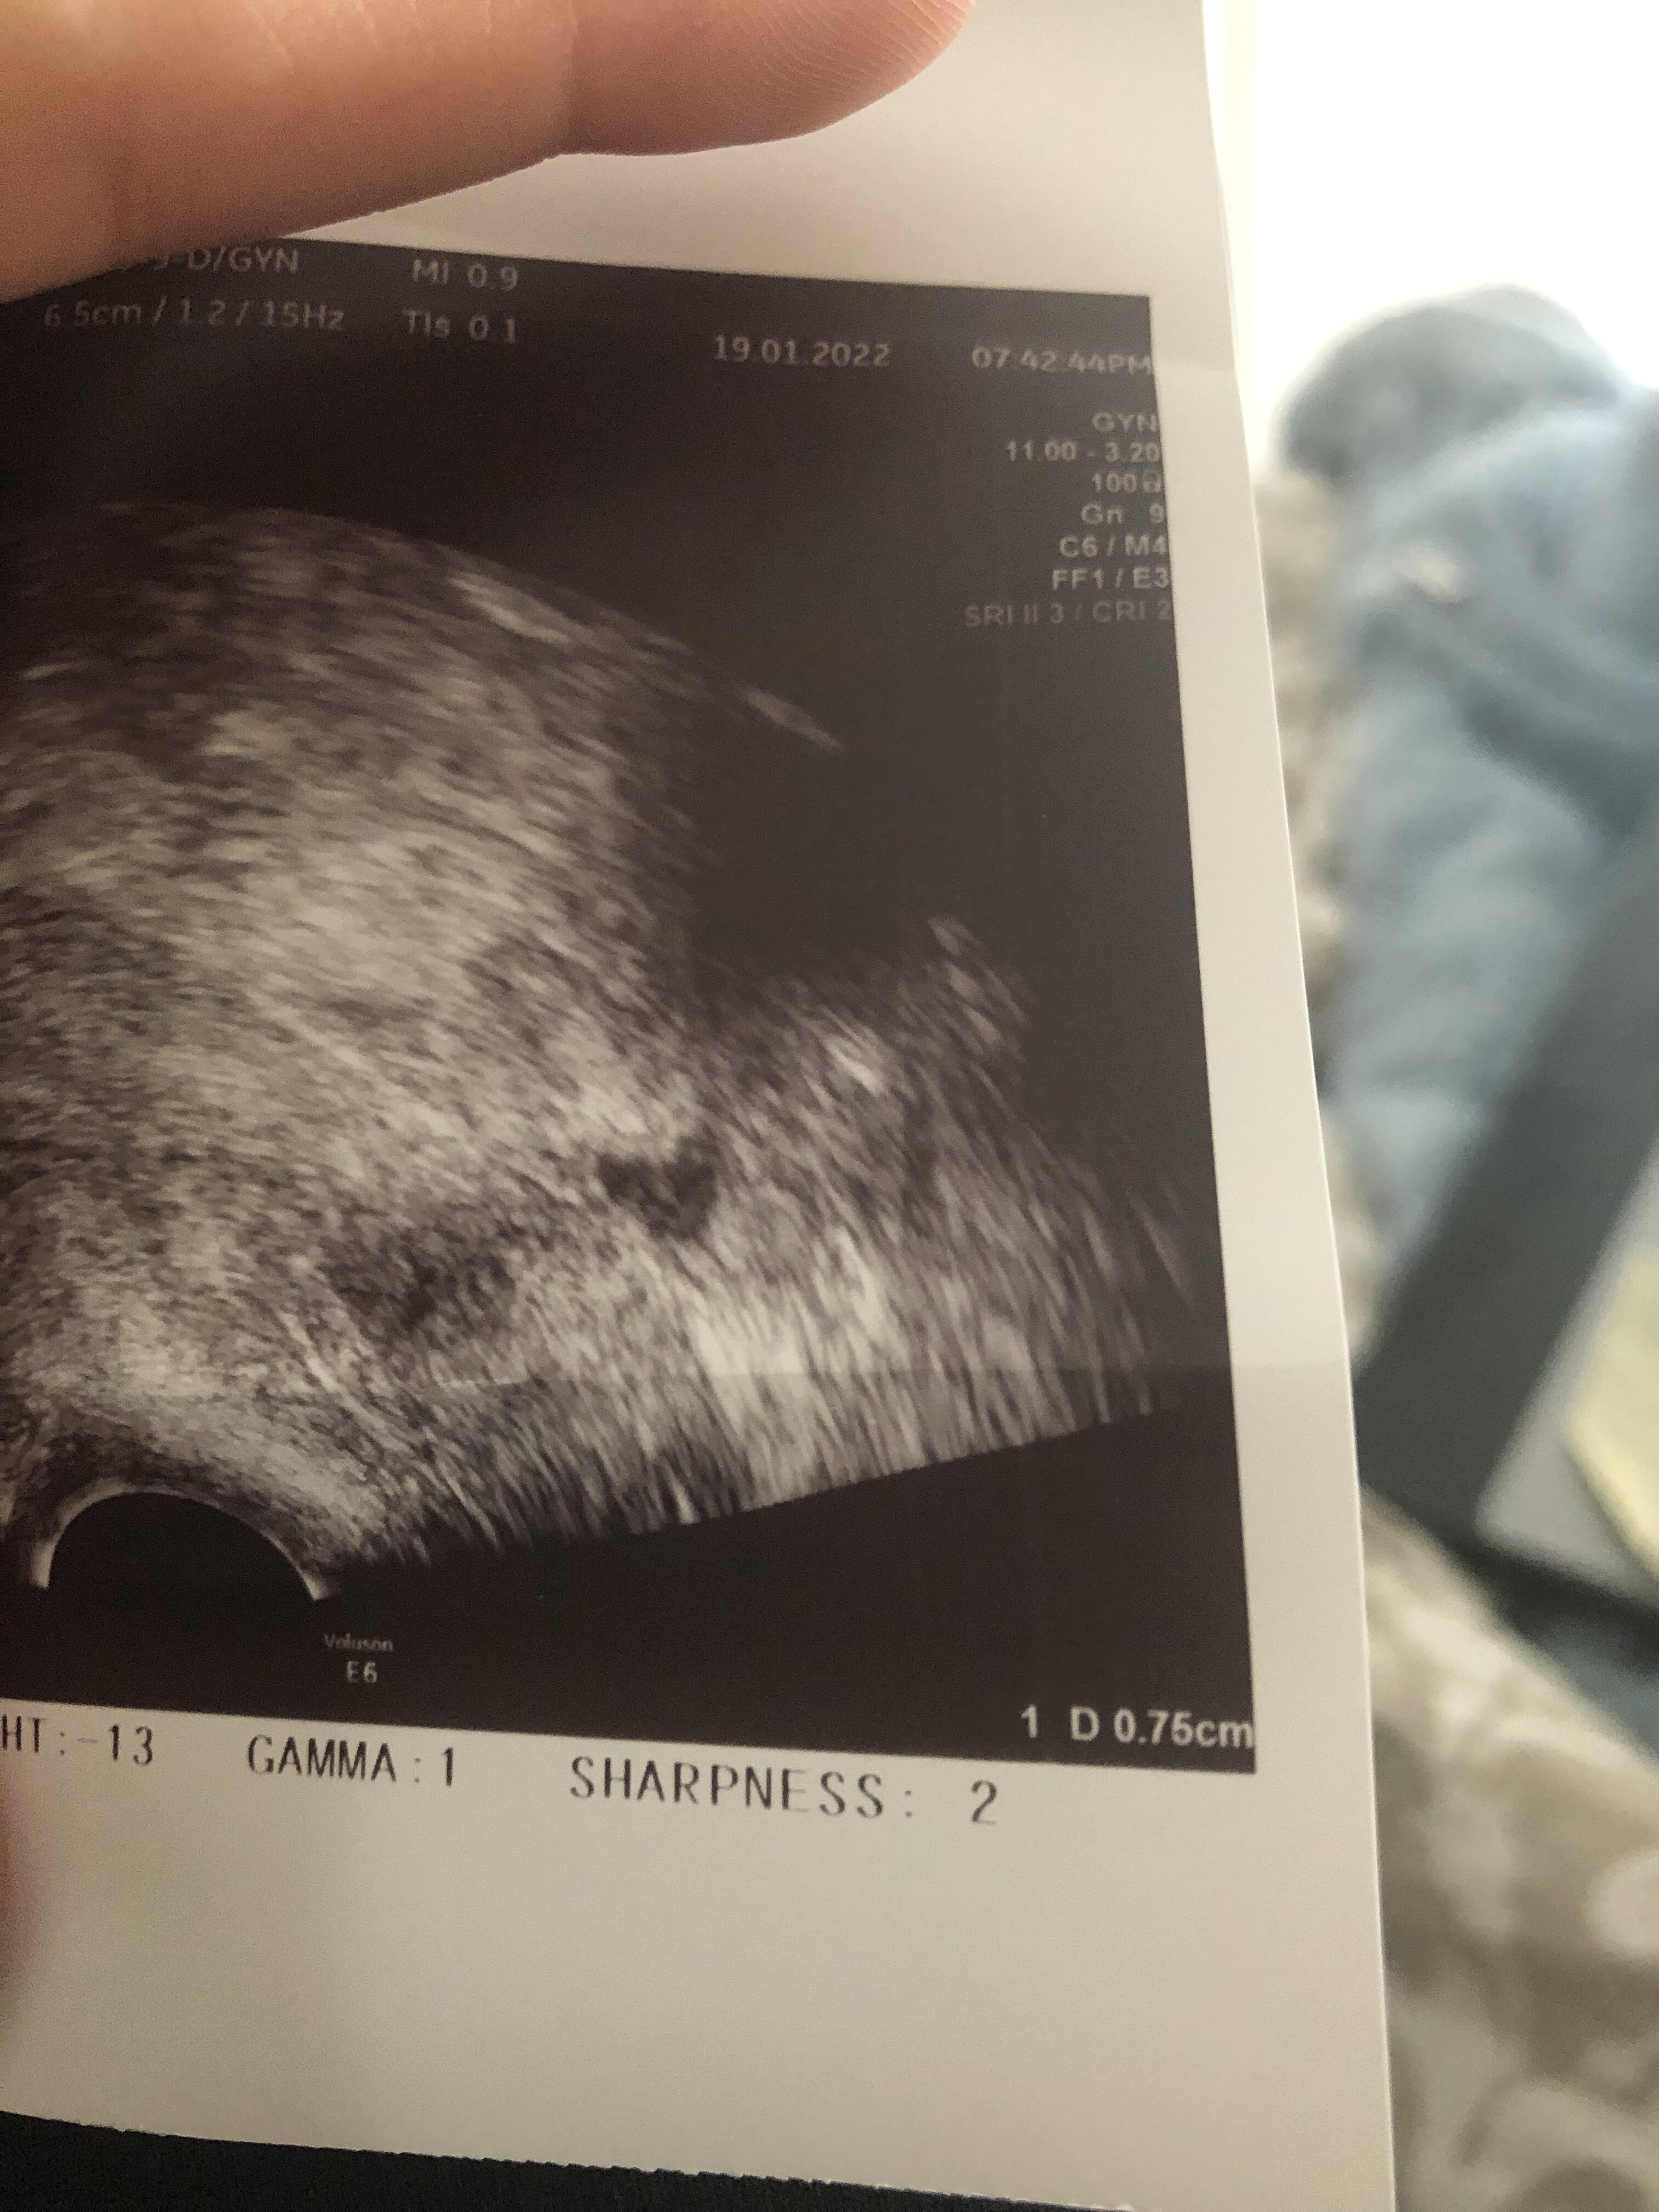

W którym miejscu na zdjęciu będzie to endometrium? To będzie to ze zdjęcia 0,75? Takie miałam w 14dc w 15 owu a w 16 0,92 jeśli dobrze odczytuje.A co masz na opisie? Powinnaś mieć grubość endometrium, wielkość jajników i wielkość pęcherzyków dominujących przynajmniej w 2 wymiarach.

A pokaż całość zdjęcia z tym wymiarem 0,75 bo ucięłaś połowę. To może być oczywiście endometrium.W którym miejscu na zdjęciu będzie to endometrium? To będzie to ze zdjęcia 0,75? Takie miałam w 14dc w 15 owu a w 16 0,92 jeśli dobrze odczytuje.

Wrzucam akurat z dnia po owu 0,92 jest o ile coś widaćA pokaż całość zdjęcia z tym wymiarem 0,75 bo ucięłaś połowę. To może być oczywiście endometrium.

Szczerze Ci powiem pierwszy raz widzę taki obraz endometrium, więc nie mam bladego pojęcia czy to to. Ale z drugiej strony nie jest to ani jajnik ani nic innego. Szkoda że nie dostałaś opisuWrzucam akurat z dnia po owu 0,92 jest o ile coś widać![]()